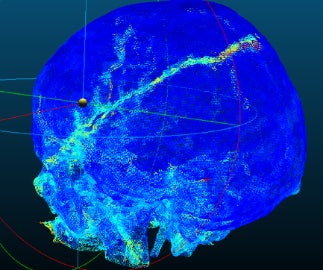

2D画像では、例えば骨折を検出する際、亀裂の方向が画像面と平行に近くなるほど映りにくくなるため、連続性や分岐のような構造の把握が難しいという課題がありました。3D画像をそのまま学習させることにより、立体的な形状が把握できるようになりました。

エクセル・クリエイツは、この技術をはじめとして、AIによって死後CTの画像解析を行い、解剖を支援するプロジェクトを鹿児島大学と共同で行っています。本プロジェクトにおいては頭蓋内出血と頭蓋骨骨折を検出するAIシステムの開発に取り組んでおり、法医学医師の数が少なく解剖実施率が低いという問題を抱える日本において、法医学医師の負担軽減に役立てられることが期待されています。